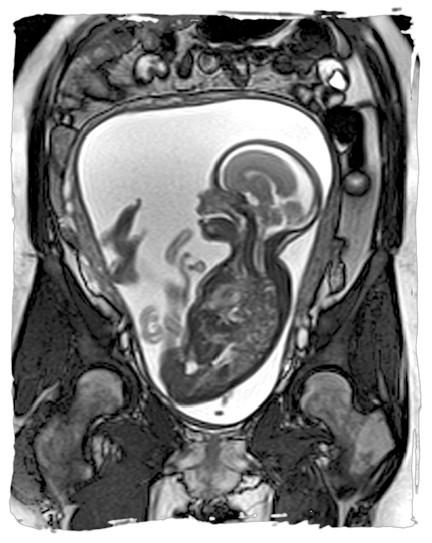

دلایل انجام ام آر آی جنین در بارداری

ام آر آی جنین ، تصویربرداری است که به کمک آن می توان اطلاعات دقیقی درباره وضعیت جنین و رحم مادر به دست آورد. این روش به...

نوبت دهی ام آر آی جفت در بارداری

ام آر آی جفت روش تصویربرداری پزشکی است که با استفاده از میدان های مغناطیسی و امواج رادیویی، تصاویر دقیقی از ساختار داخلی...